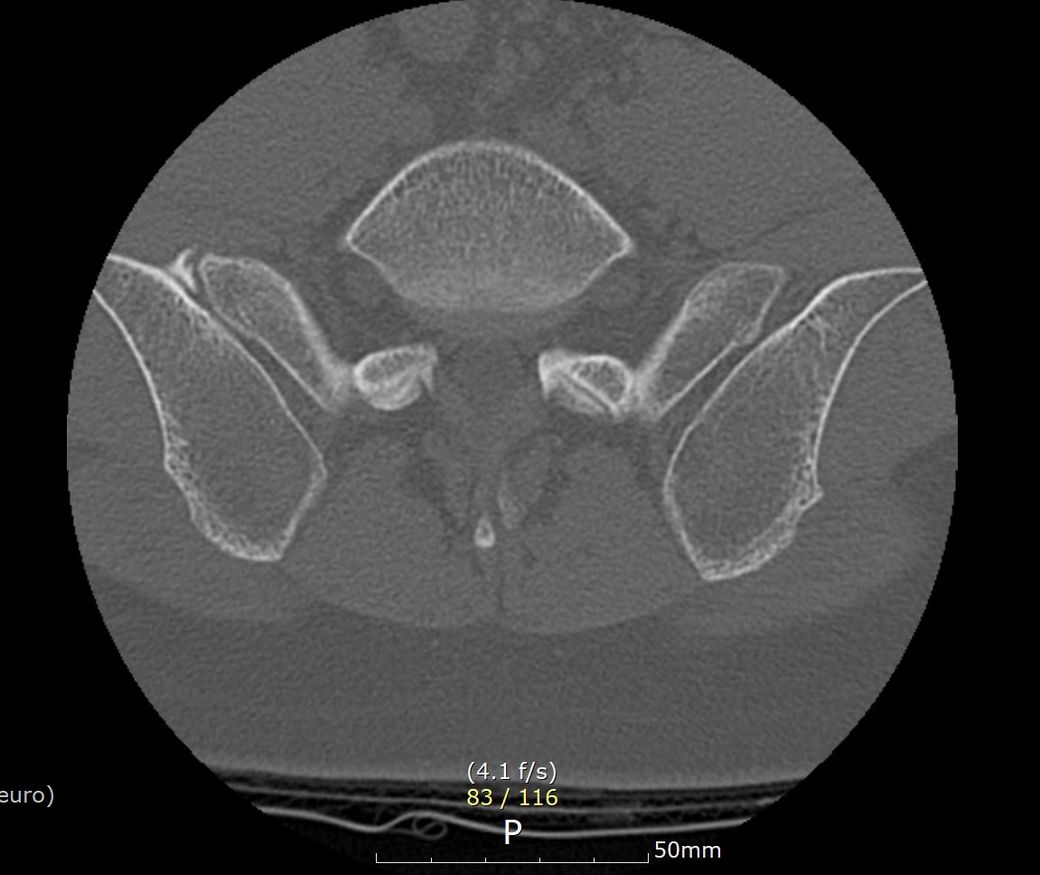

심할때는 1시간 걷다가 갑자기 골반과 옆구리가 알배기는듯이? 근육통이 심한듯이 느낌이와서 잠시 앉아서 쉬었습니다. ct영상으로도 디스크로 때문에 아프기엔 정상적인 정도라 하셔서 왜 아픈지 모르겠네요 . 현재 옆구리 좌,우 ,골반뒤쪽과 천추 꼬리뼈 또한 통증이 있으며 자고 일어나면 통증이 시작되고있습니다. 무엇때문인지 답답합니다. CT또한 촬영 했습니다.

Pneumocyst, iliac side of left sacroiliac joint.

1. Mild disc lesions at T12-L1: T12-L1 수준에서 경미한 디스크 변성이 관찰되었으며, 좌측 중앙에 헤르니아(디스크 탈출)와 T12 하단 판의 약간의 고리돌기 파열이 있습니다. 이는 해당 부위의 통증을 유발할 수 있습니다.

2. L4-5 mild bulging: L4-5 수준에서 경미한 디스크 돌출이 있습니다. 이는 허리통증과 연관될 수 있지만 심각한 정도는 아닙니다.